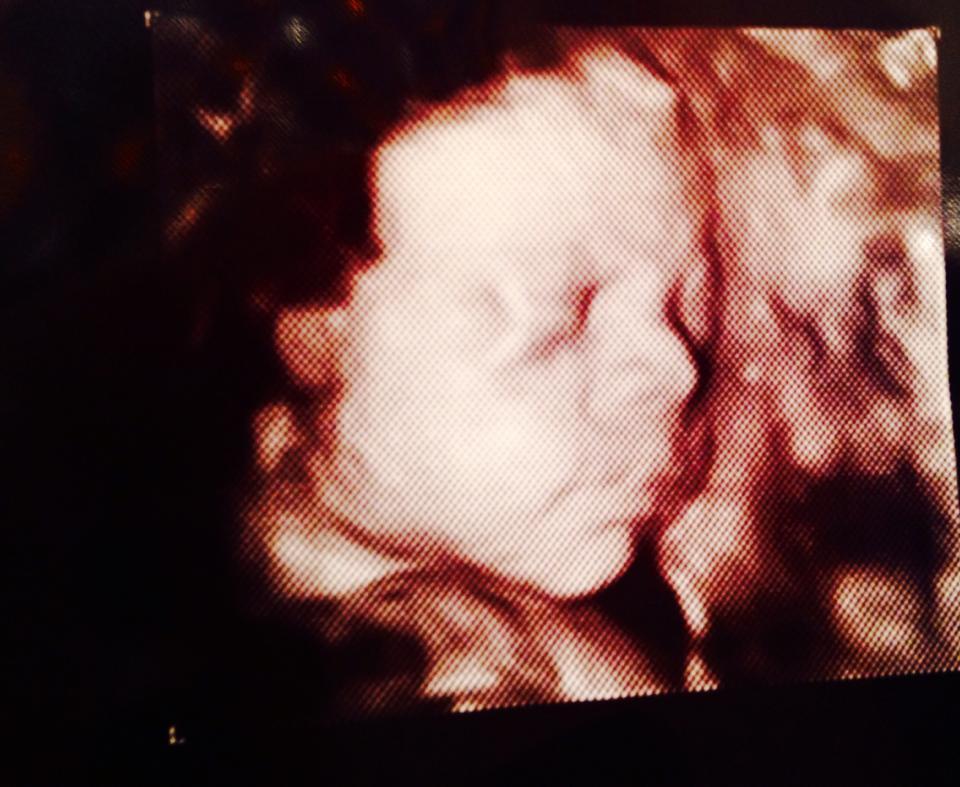

Llegamos y el ginecólogo de turno era súper bueno. Se creyó mi cuento del dolor abdominal y me hizo una ecografía para certificar que todo estaba bien. Y sí que lo estaba. Tenía a mi Joaqui con el corazón latiendo a toda velocidad. Pero bien dicen que no hay «crimen perfecto» (en este caso sería «mentira perfecta») así que habían llamado a mi ginecólogo para reportarle mi ingreso a emergencia y él había decidido acercarse para ver a su acontecida paciente, o sea a mí.

Y así pasaban los meses y cada uno más particular que otro. Ahora, esa no fue la única vez que tuve la imperiosa necesidad de que me hagan una ecografía. Fueron muchas. Tenía loco a Rubén e incrementé los ingresos de Inppares, adonde acudí por una y otra ecografía que el seguro particular, obviamente, no lo cubriría. Cuando Joaquín se comenzó a dejar sentir con sus patadas, hipo y constantes movimientos, mis necesidades de ecografías “extras» fueron reduciéndose.